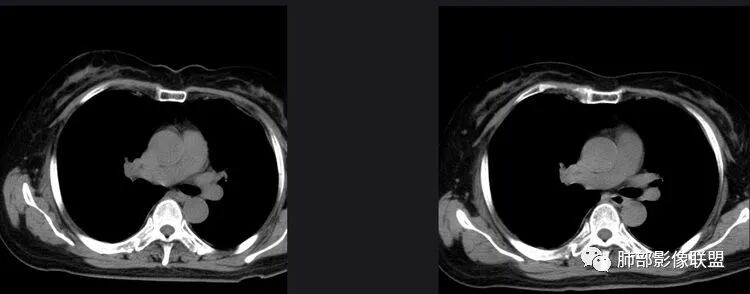

以下是两个时间点左右对比

2019.11.26  👇                           2020.01.20👇                                            2019.11.26片

2020.01.20片

2.早期CT表现左肺上叶不规则团块影,呈混合密度,以实性密度为主,但整体密度偏低,周围隐约见磨玻璃密度影。

边缘不规则,前内侧缘见小叶间隔限制(注意,并非典型深分叶),病灶外侧细长毛刺,病灶内有小空泡及空气支气管征,有胸膜牵拉征象。

上述征象均提示病灶为恶性病灶,但边缘特征及空气支气管征似乎有别于常见的浸润性腺癌及MALT。

3.复查影像显示病灶整体大小变化不明显,其内空泡消失,但是周围磨玻璃影趋于似清非清,整体病灶收缩力中等偏弱,均提示粘液腺癌的可能性大。